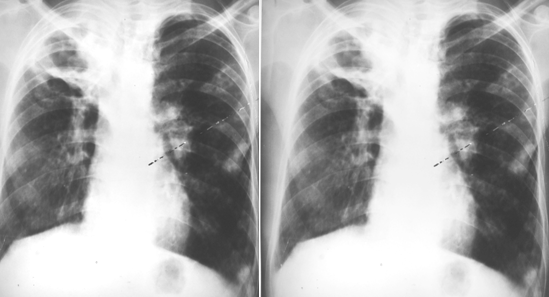

右肺下叶背段大叶性肺炎正侧位

胸部正侧位片:右肺下叶背段见片状、三角形致密影,边缘模糊(箭头所指)

右肺中叶大叶性肺炎正侧位

胸部正侧位片:右肺中叶见片状致密影,边缘模糊,局部呈剪影样改变(红圈所示)